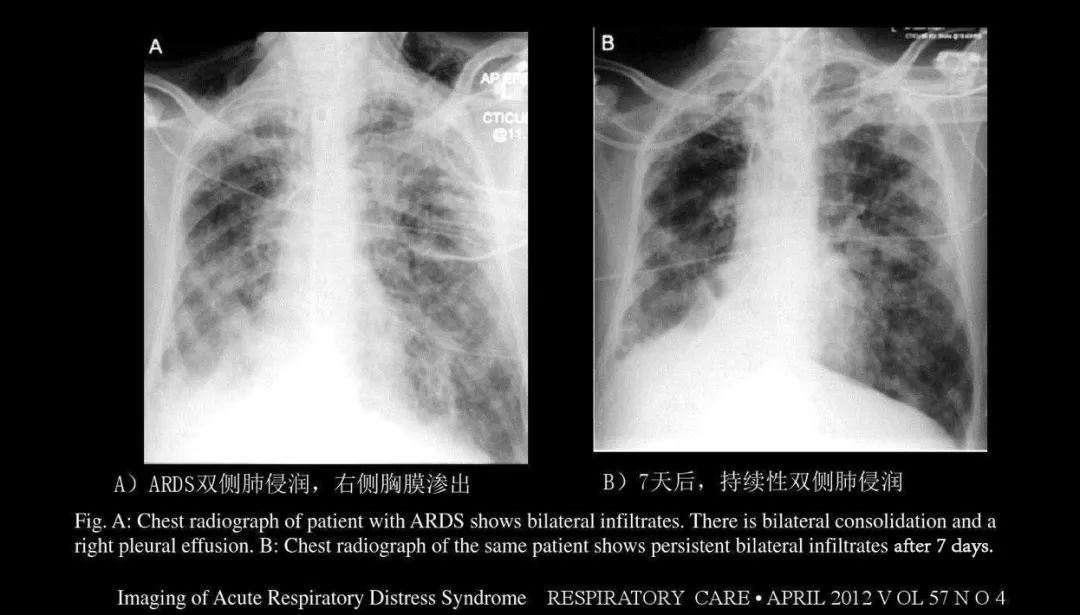

➤ 急性肺水肿